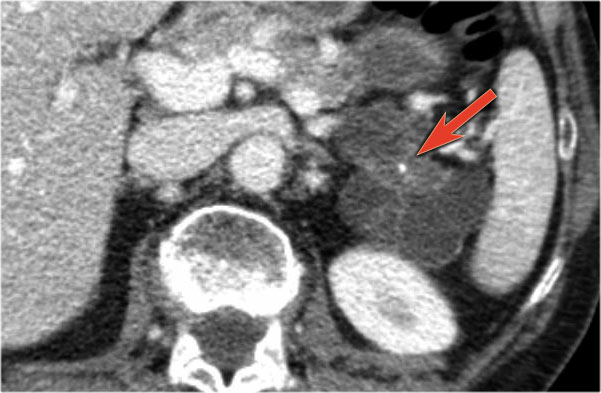

Bệnh nhân này bị viêm tụy mạn tính.

Lưu ý các vôi hóa ở đầu tụy (mũi tên cong).

Có nhiều nang giả tụy lan dài vào tận trung thất, gây chèn ép tim (mũi tên đỏ).